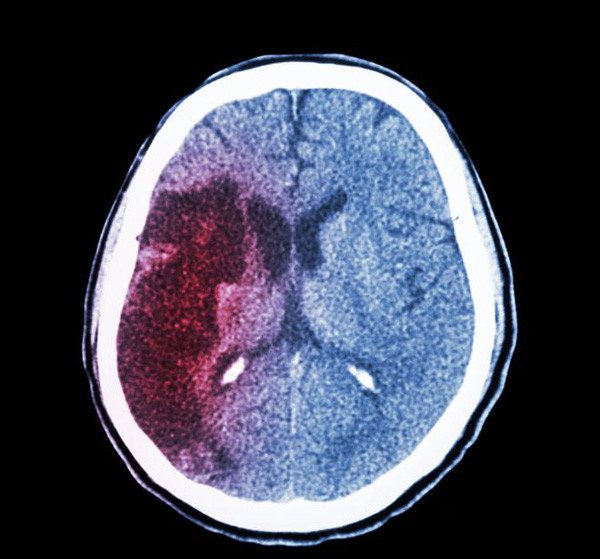

| Xuất huyết não là một loại đột quỵ, xảy ra khi máu thoát khỏi thành mạch, tràn vào mô não, gây tổn thương não. Xuất huyết não có tỷ lệ mắc khá cao, thường xảy ra ở những người trên 50 tuổi. (Ảnh: ABLW, minh họa) |

| Bệnh nhân xuất huyết não nặng có tỷ lệ tử vong cao, tiên lượng phụ thuộc chủ yếu vào kích thước khối máu tụ trong não. May mắn thay, trước khi tình trạng xuất hiện, cơ thể sẽ phát những dấu hiệu cảnh báo xuất huyết não điển hình. |